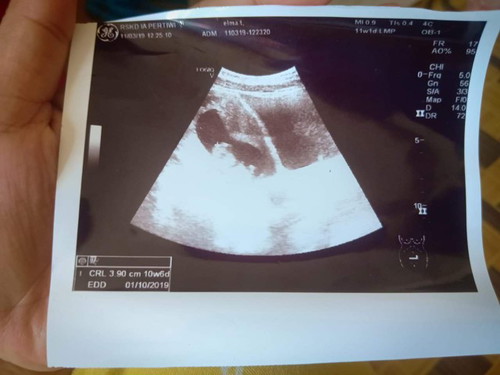

Kemarin pas bulan 3 tgl 11 USG dedeknya Usia 10W6D tapi kemarin pas usg tgl 12/07/19 kata dokternya Usianya baru 26W pdhl dari hasil perhitungan aku harusnya 29W3D ? ko bisa beda yah bun?

Umur janin yg tertera di usg itu dihitung dari besar dan berat janin Semakin besar janin dari usia umum kehamilan maka usia yg di tampilkan di usg akan lebih tua, kalau beratnya kurang dari usia umum maka usia yg di tampilkan di usg akan lebih muda Setiap usg tgl hpl dan usia janin bisa berubah Nurut hitungan bunda saja